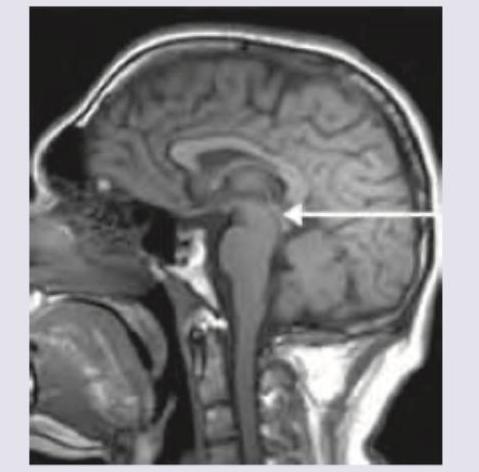

A 60-year-old man presents with history of memory loss and fatigue. On examination, he has bradykinesia with axial rigidity. Resting tremor is absent and patient has broad-based gait with tendency to fall. MRI was done. All are true about the condition except:

Explanation: ***Intracranial hypotension*** - Progressive Supranuclear Palsy (PSP) is characterized by **brain atrophy**, not intracranial hypotension, and specifically shows atrophy of the **midbrain** and superior cerebellar peduncle. - Intracranial hypotension typically presents with **postural headaches**, which were not mentioned in the patient's presentation. *Poor response to levodopa* - Patients with PSP often show a **poor or transient response to levodopa**, which distinguishes it from Parkinson's disease. - This is due to the widespread neurodegeneration affecting areas beyond the dopaminergic pathways. *Gaze palsy* - **Vertical supranuclear gaze palsy**, particularly affecting downward gaze, is a **hallmark symptom** of PSP. - This manifests as difficulty moving the eyes voluntarily, especially downwards, while reflex eye movements (e.g., vestibulo-ocular reflex) may be preserved initially. *Humming Bird appearance* - The **Hummingbird sign (or Penguin sign)** is a characteristic MRI finding in PSP, referring to the **midbrain atrophy** with relative preservation of the pons, resembling a hummingbird. - The image provided shows significant midbrain atrophy, consistent with this sign.